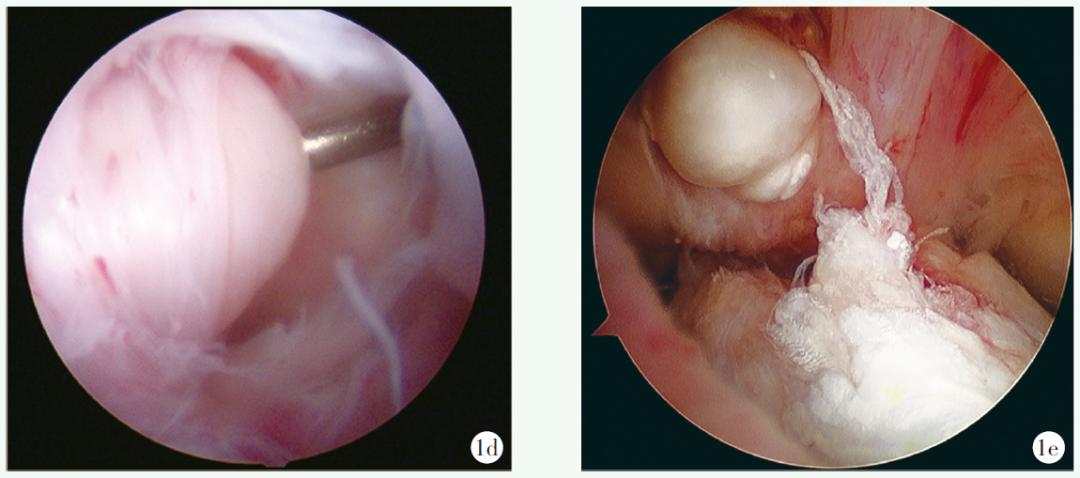

共有20例患者翻修时就诊主诉为外伤(再次外伤),12例主诉为无明显诱因(重建术后恢复不佳),4例就诊时主诉为术后感染。根据骨隧道位置是否正确进行再次分层后发现,17例隧道正常翻修患者的外伤主诉占比最高,共有12例(70.59%),无明显诱因者有3例(17.65%),术后感染患者2例(11.76%);16例骨隧道位置欠佳患者中,6例(37.50%)患者为外伤主诉,无明显诱因者有9例(56.25%),术后感染者1例(6.25%)。所有病例均在关节镜下进行ACL翻修手术及处理合并损伤。镜下见所有重建的ACL均发生了断裂、吸收或松弛失效(图1d~1f)。36例翻修手术中,23例使用了自体肌腱,10例使用了LARS人工韧带,2例使用了同种异体肌腱,1例因自体肌腱过细(≤6mm)而使用了自体肌腱加同种异体肌腱进行了翻修。

图1 患者,男,34岁,于外院初次重建术后3年内逐渐出现活动后绞索等症状,在本次翻修手术中使用了自体肌腱,并选择了全新的股骨及胫骨隧道,ACL翻修的术前影像与镜下所见1a, 1b:右膝侧位X线片及CT矢状位显示初次重建术后股骨隧道位置偏前1c:镜下见LARS人工韧带松弛失效,LARS人工韧带表面覆盖大量滑膜组织1d:镜下见同种异体肌腱松弛失效1e:镜下见初次重建时自体肌腱断裂,断端挛缩并吸收为球状